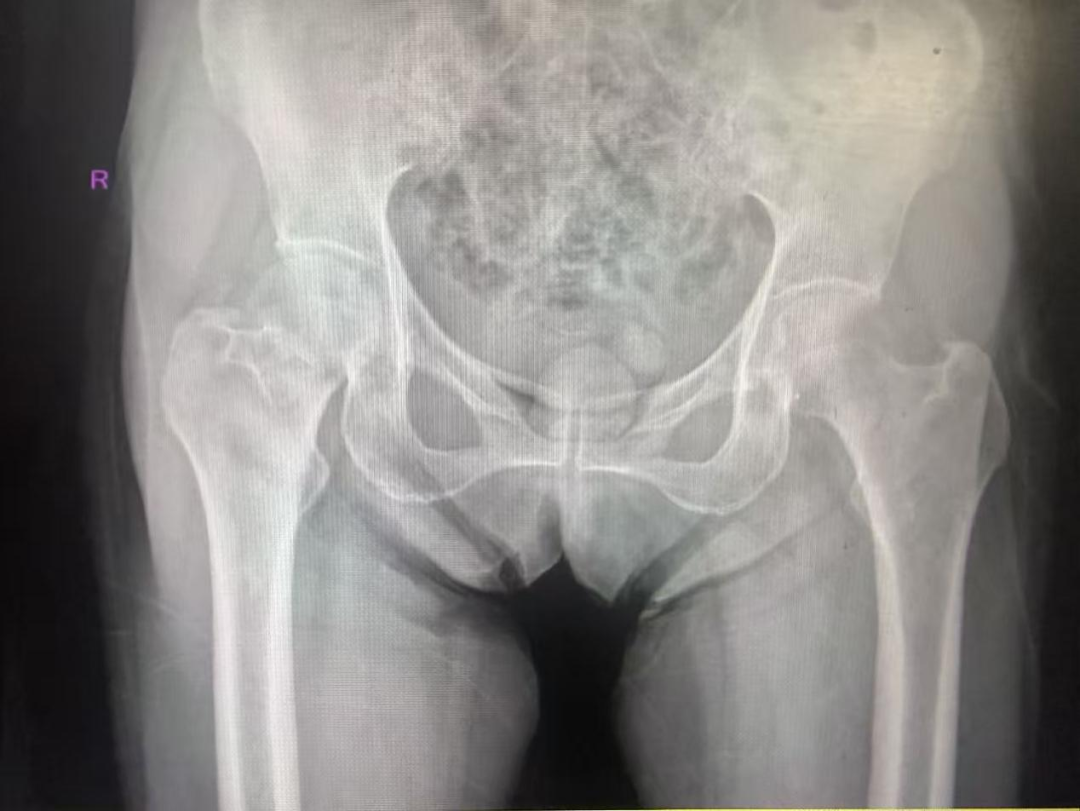

因雨后路面湿滑,李奶奶不慎重重摔倒,当即觉得右髋部剧痛,无法动弹。好心路人将她送到医院,经急诊检查,确诊为“右侧股骨颈骨折”(头下型,Garden IV型)。对于高龄、伴有骨质疏松的李奶奶而言,这无疑是一个严峻的挑战。

股骨颈骨折常被称为“人生最后一次骨折”,对高龄患者尤其危险,保守治疗卧床时间长,极易引发肺部感染、泌尿系感染、褥疮、下肢深静脉血栓等严重并发症,危及生命。

髋关节置换术是股骨颈骨折的常见治疗方案,可以尽快恢复活动能力,避免长期卧床风险。然而,李奶奶年事已高,手术耐受性是家人首要的担忧;高龄、基础疾病的存在,也让部分医生对手术风险持谨慎态度。

手术,存在风险;不手术,却意味着李奶奶余生可能再无法完成坐起、站立等基础动作。家属们带着李奶奶的影像资料,辗转咨询了多家医院,内心充满了焦虑与无助。